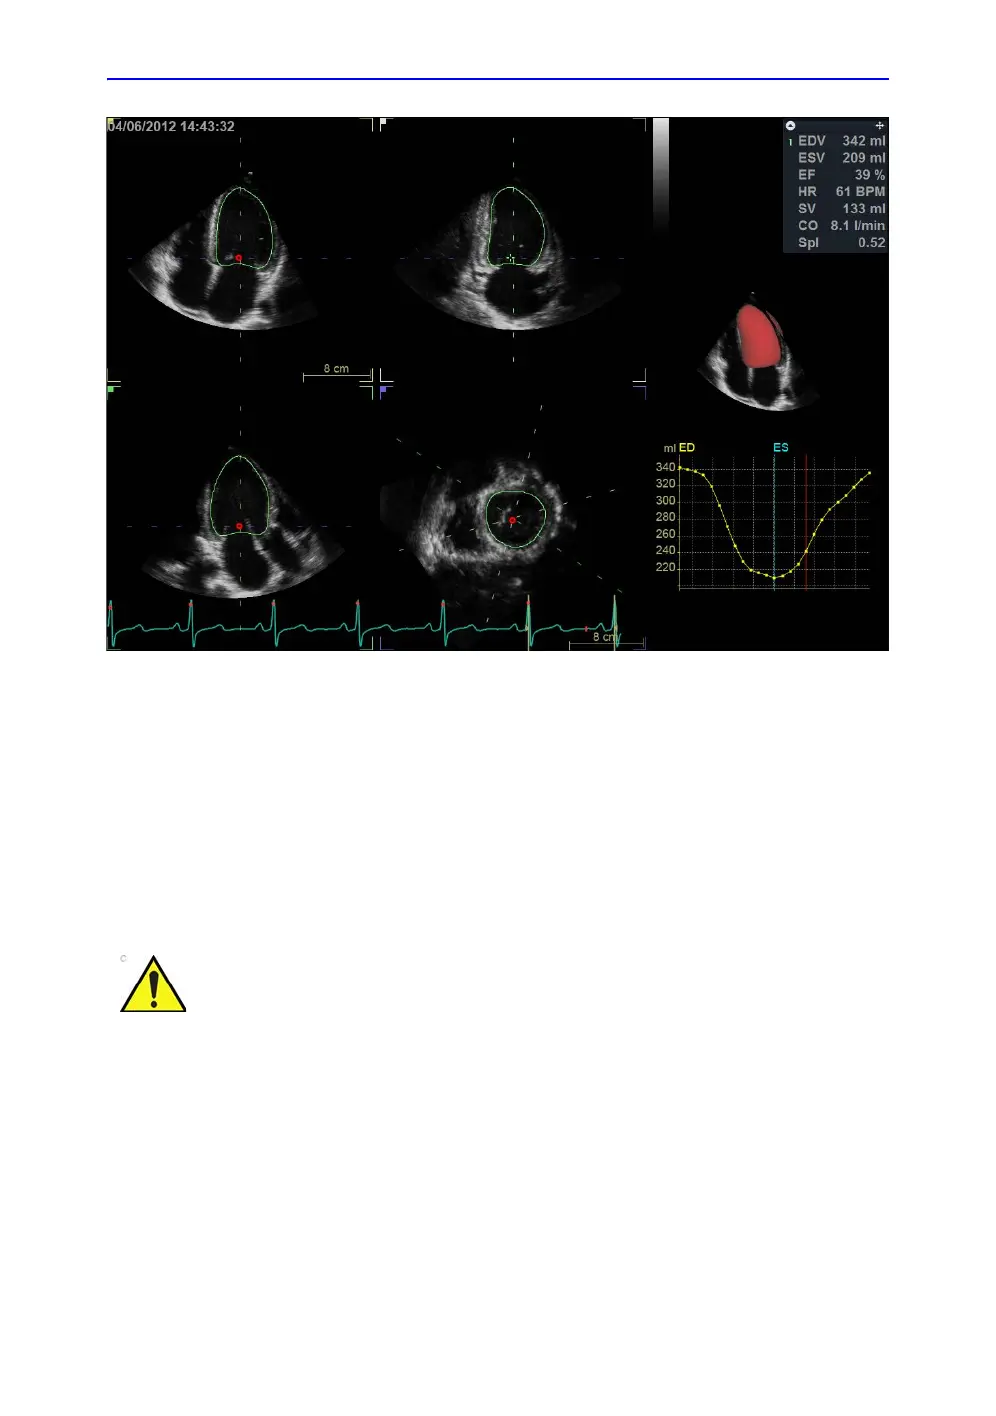

Figure 8-30. The Volume waveform screen

1. Press Approve & Exit to store the measurements shown in

the Measurement result table.

The measurements are transferred to the Worksheet.

To exit without approving, press Cancel.

NOTE: Measurements that are not approved will not be saved.

The measurement should not be approved if a significant part

(more than 25%) of the left ventricular wall or the detected

contours are outside the ultrasound sector.